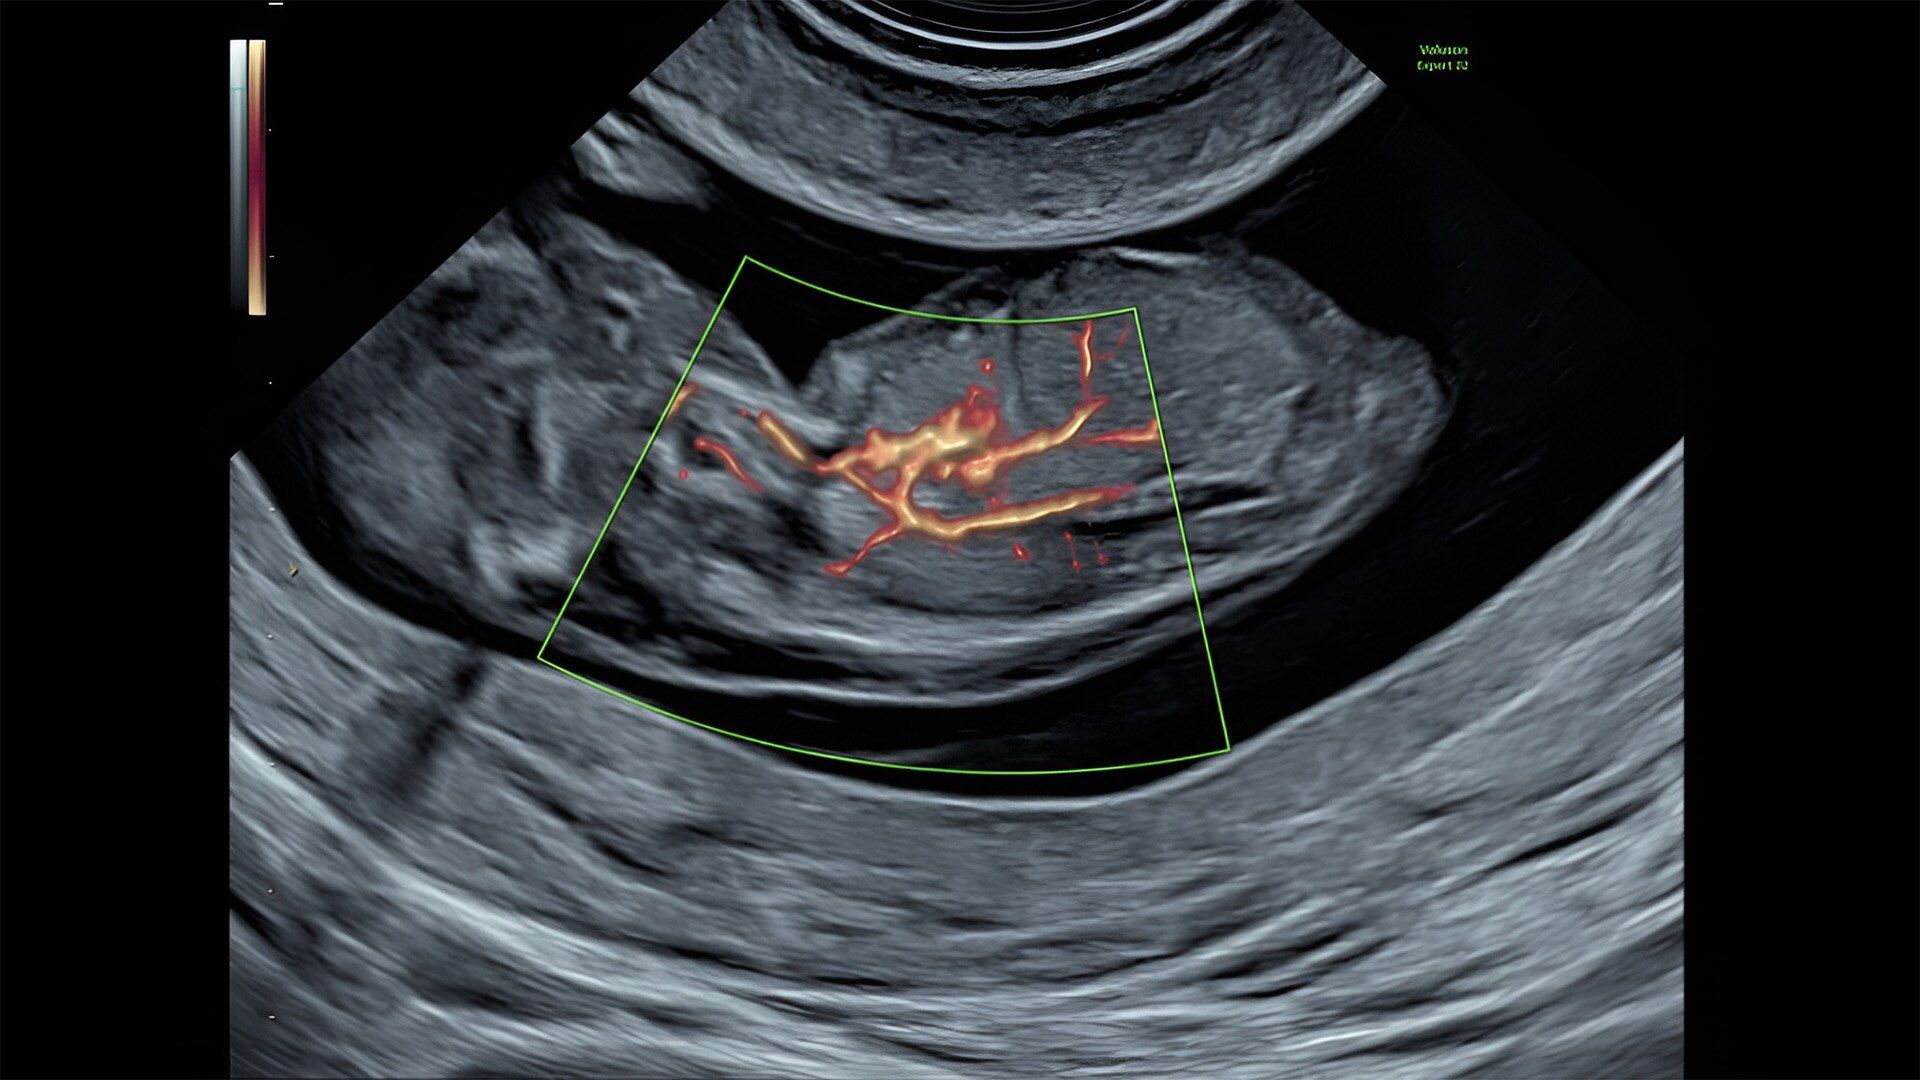

Pelvic health

Offer patient answers faster with Ai-based automation tools